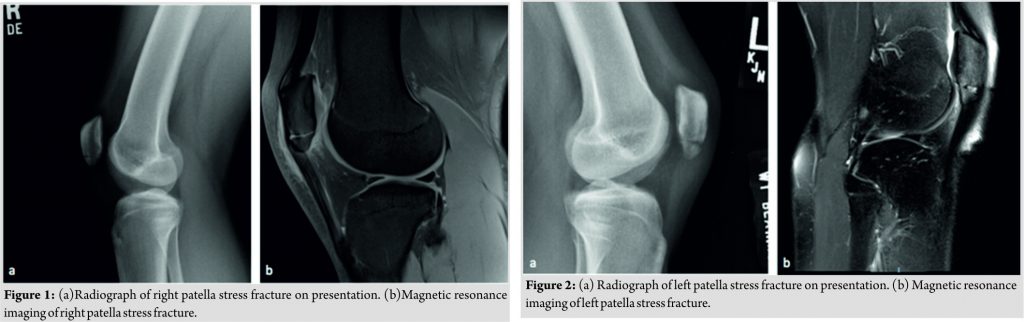

A 17-year-old female high school senior gymnast, who had signed a full scholarship offer for Division I collegiate gymnastics, initially presented to our office after 3 months of anterior knee pain. Her pain had gradually worsened in severity over this time period and was, especially, painful with dismounts and jumping activities. She had previously sought treatment with her primary care physician who had diagnosed her with patellar tendonitis and was being managed conservatively with the help of the school’s athletic trainer. She denied any history of amenorrhea, eating disorders, or previous stress fractures. Initial radiographs obtained in our office revealed what appeared to be a non-displaced transverse fracture of the inferior pole of the patella (Fig. 1).

An MRI was obtained that confirmed the diagnosis of a patellar stress fracture and ruled out any patella tendon or intra-articular pathology (Fig. 1). The patient was immobilized in a hinged knee brace, locked in extension. She was also prescribed Vitamin D and calcium supplementation as well as daily use of an Exogen® LIPUS system(Bioventus LLC, Durham, NC, USA). It was discussed with the patient that since the injury was 2–3 months’ old, she was at a higher risk for failing conservative treatment, which would require operative fixation. At 1month follow-up, radiographs were obtained that showed early callus formation, and her examination revealed a clinical decrease in her pain. She was then progressed to weight bearing as tolerated with gradual increase in her range of motion guided by physical therapy. At 2 months, radiographs showed fracture healing, and we began gradual reintegration of gymnastics with limitations on tumbling/dismounting/jumping activities. At 3 months, she was allowed to return to full competition. After approximately 1year of returning to sport and competing as a collegiate gymnast, she unfortunately began to develop similar symptoms as before, now in her contralateral knee. She presented back to our office where we confirmed the diagnosis of a stress fracture of the inferior pole of the contralateral patella, similar to her previous injury (Fig. 2). At that visit, radiographs revealed complete healing of her prior stress fracture from 1year ago. She was given the same conservative management plan of a period of immobilization in a hinged knee brace locked in extension, Vitamin D and Calcium supplementation, daily use of LIPUS, and later progressed to physical therapy with guided return to gymnastic activities. At 3 months, she was pain free, and a Knee Injury and Osteoarthritis Outcome Score (KOOS) survey was obtained [Graph1][20]. With the KOOS showing favorable results, in addition to being pain free, the patient was allowed a full return to competition(Fig. 3). She is now 3 years from injury on the right knee and 2years from injury on the left knee and continues to compete at the Division I collegiate level without pain(Fig. 4).